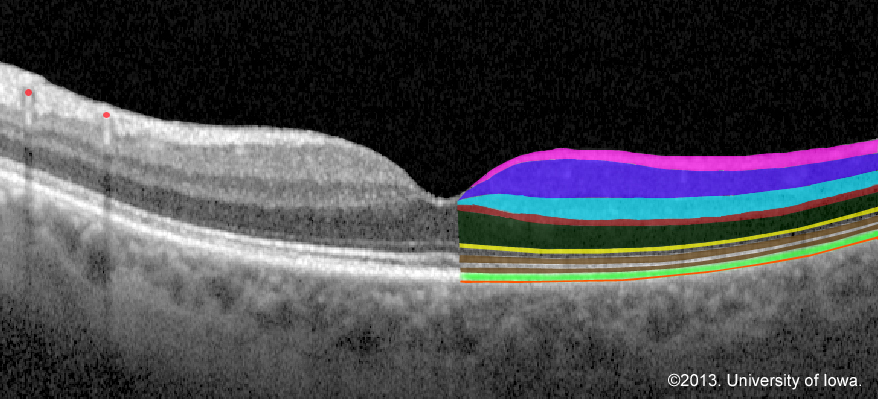

Optical coherence tomography (OCT) image of the retina with the layers colored for clarification

Figure 1. Optical coherence tomography (OCT) image of the retina with the layers colored for clarification on the right. From top to bottom are the internal limiting membrane, nerve fiber layer, ganglion cell layer (pink), inner plexiform layer (purple), inner nuclear layer (turquoise), outer plexiform layer (red), outer nuclear layer (cell bodies of the photoreceptors; dark green), external/outer limiting membrane (yellow), and the photoreceptor layer (internal and external segments; brown). The retinal pigment epithelium is immediately underneath the retina (bright green). Bruch’s membrane (orange) is a thin membrane that separates the retinal pigment epithelium from the underlying highly vascular choroid. The retinal vasculature (red dots upper left) cast shadows on the OCT.